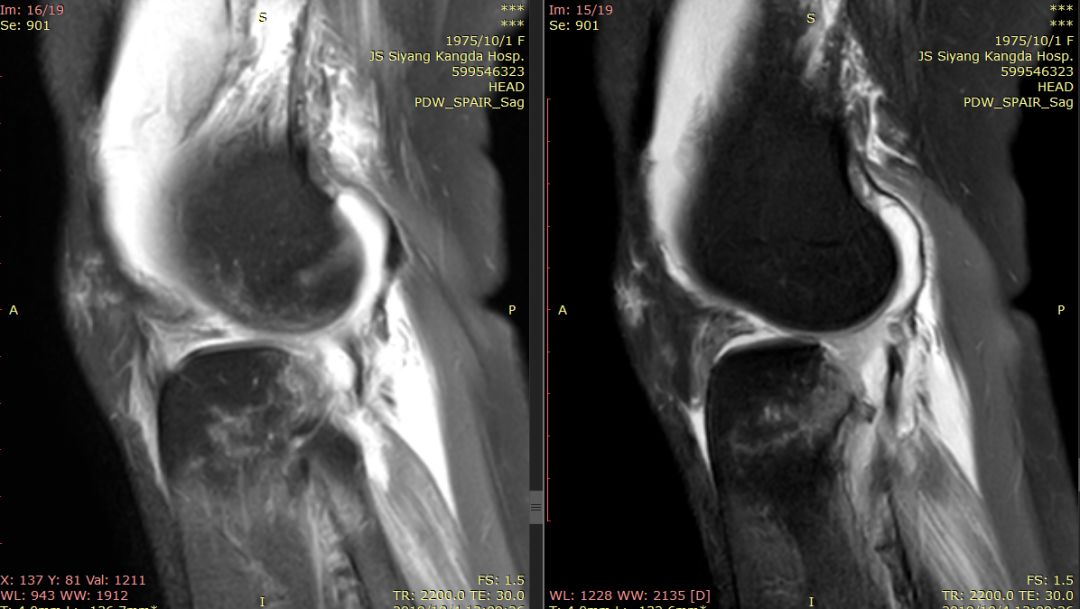

下图标记的是外侧半月板的撕裂

下图示外侧副韧带损伤 腘肌腱损伤 髂胫束连续

内侧副韧带损伤

膝后肌群损伤